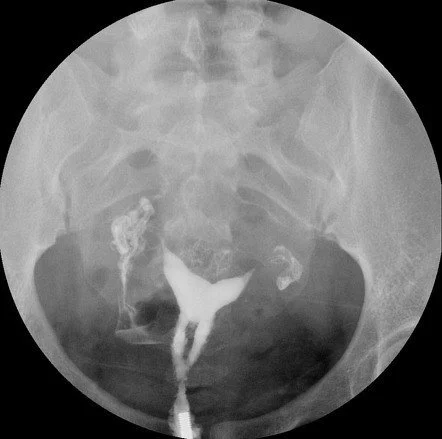

Diagnosis

• Hysteroscopy (gold standard)

• Hysterosalpingography

• Transvaginal ultrasound with saline infusion